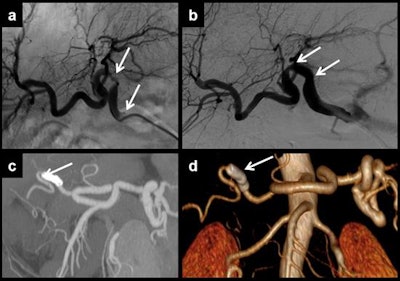

Multiplanar and 3D curved reformatting are useful to measure the vessel lumen in cases of multifocal stenosis of the hepatic artery. Each stenosis should be treated separately. In this case, angiography demonstrated two points of stenosis (a, b). Two stents were placed for treatment. Control CT showed that stents had been correctly placed. Distal artery flow is shown in the maximum intensity projection reconstruction (c) and in the volume-rendered reconstruction (d)."Stenosis may progress to thrombosis. So, stenosis and thrombosis are two entities of the same spectrum of vascular complications of liver transplantation," the authors wrote. "Stenosis can lead to splenic steal artery syndrome. It usually occurs in the first three months, but this time shows differences between patients, describing cases that happen even several years after surgery. Doppler ultrasound is the most useful technique to show this complication, as explained for thrombosis."